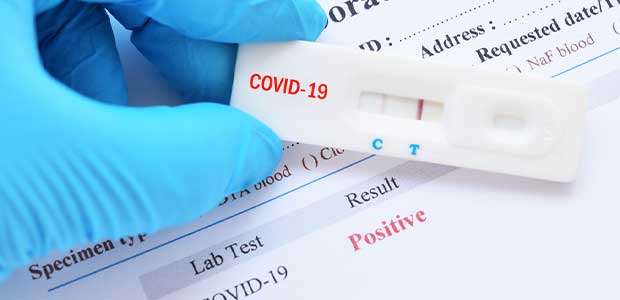

Creating an effective program to test for substance abuse in the workplace can be difficult when faced with modern day trends and challenges.

New guidelines published last week include what to do if you are exposed to COVID-19.